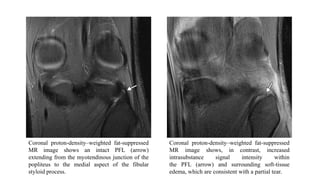

Coronal proton-density–weighted fat-suppressed

MR image shows an intact PFL (arrow)

extending from the myotendinous junction of the

popliteus to the medial aspect of the fibular

styloid process.

MR image shows, in contrast, increased

intrasubstance signal intensity within

the PFL (arrow) and surrounding soft-tissue

edema, which are consistent with a partial tear.